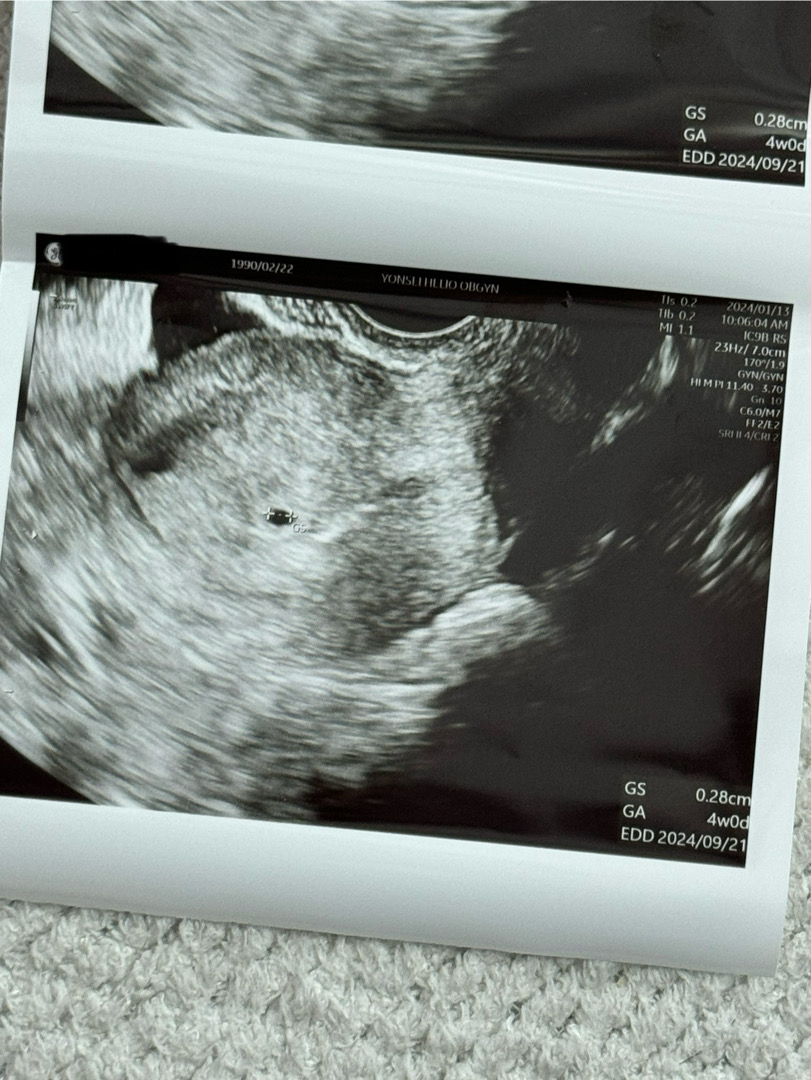

초음파 사진좀 봐주세요 :)

안녕하세요 :) 5주차에 아기집보고왔는데 초음파사진엔 4주차라고 나와있어서 ㅠㅠ 제가 4주차인지 5주차인지 모르겠어요 ㅠㅠ

저도 마지막생리나 그런 계산으로는 5주차일때 방문했는데 이 초음파사진과 크기가 비슷하고 4주로 추정된다고 하시더라구요! 사람마다 착상되는 시기가 다를 수 있어 차이가 있는거같은데 초음파로 주수를 생각하시면 될 것 같아요😊아마 4주 끝자락이 아니실가요? 저정도 크기 초음파보고 2주뒤에 심장소리 듣고왔어요~!

초음파는 기계로 측정하는거라 앞으로 보실때도 계속 주수는 바뀌어요~ 의사샘이 말해주는 주수가 맞는거에용🙂